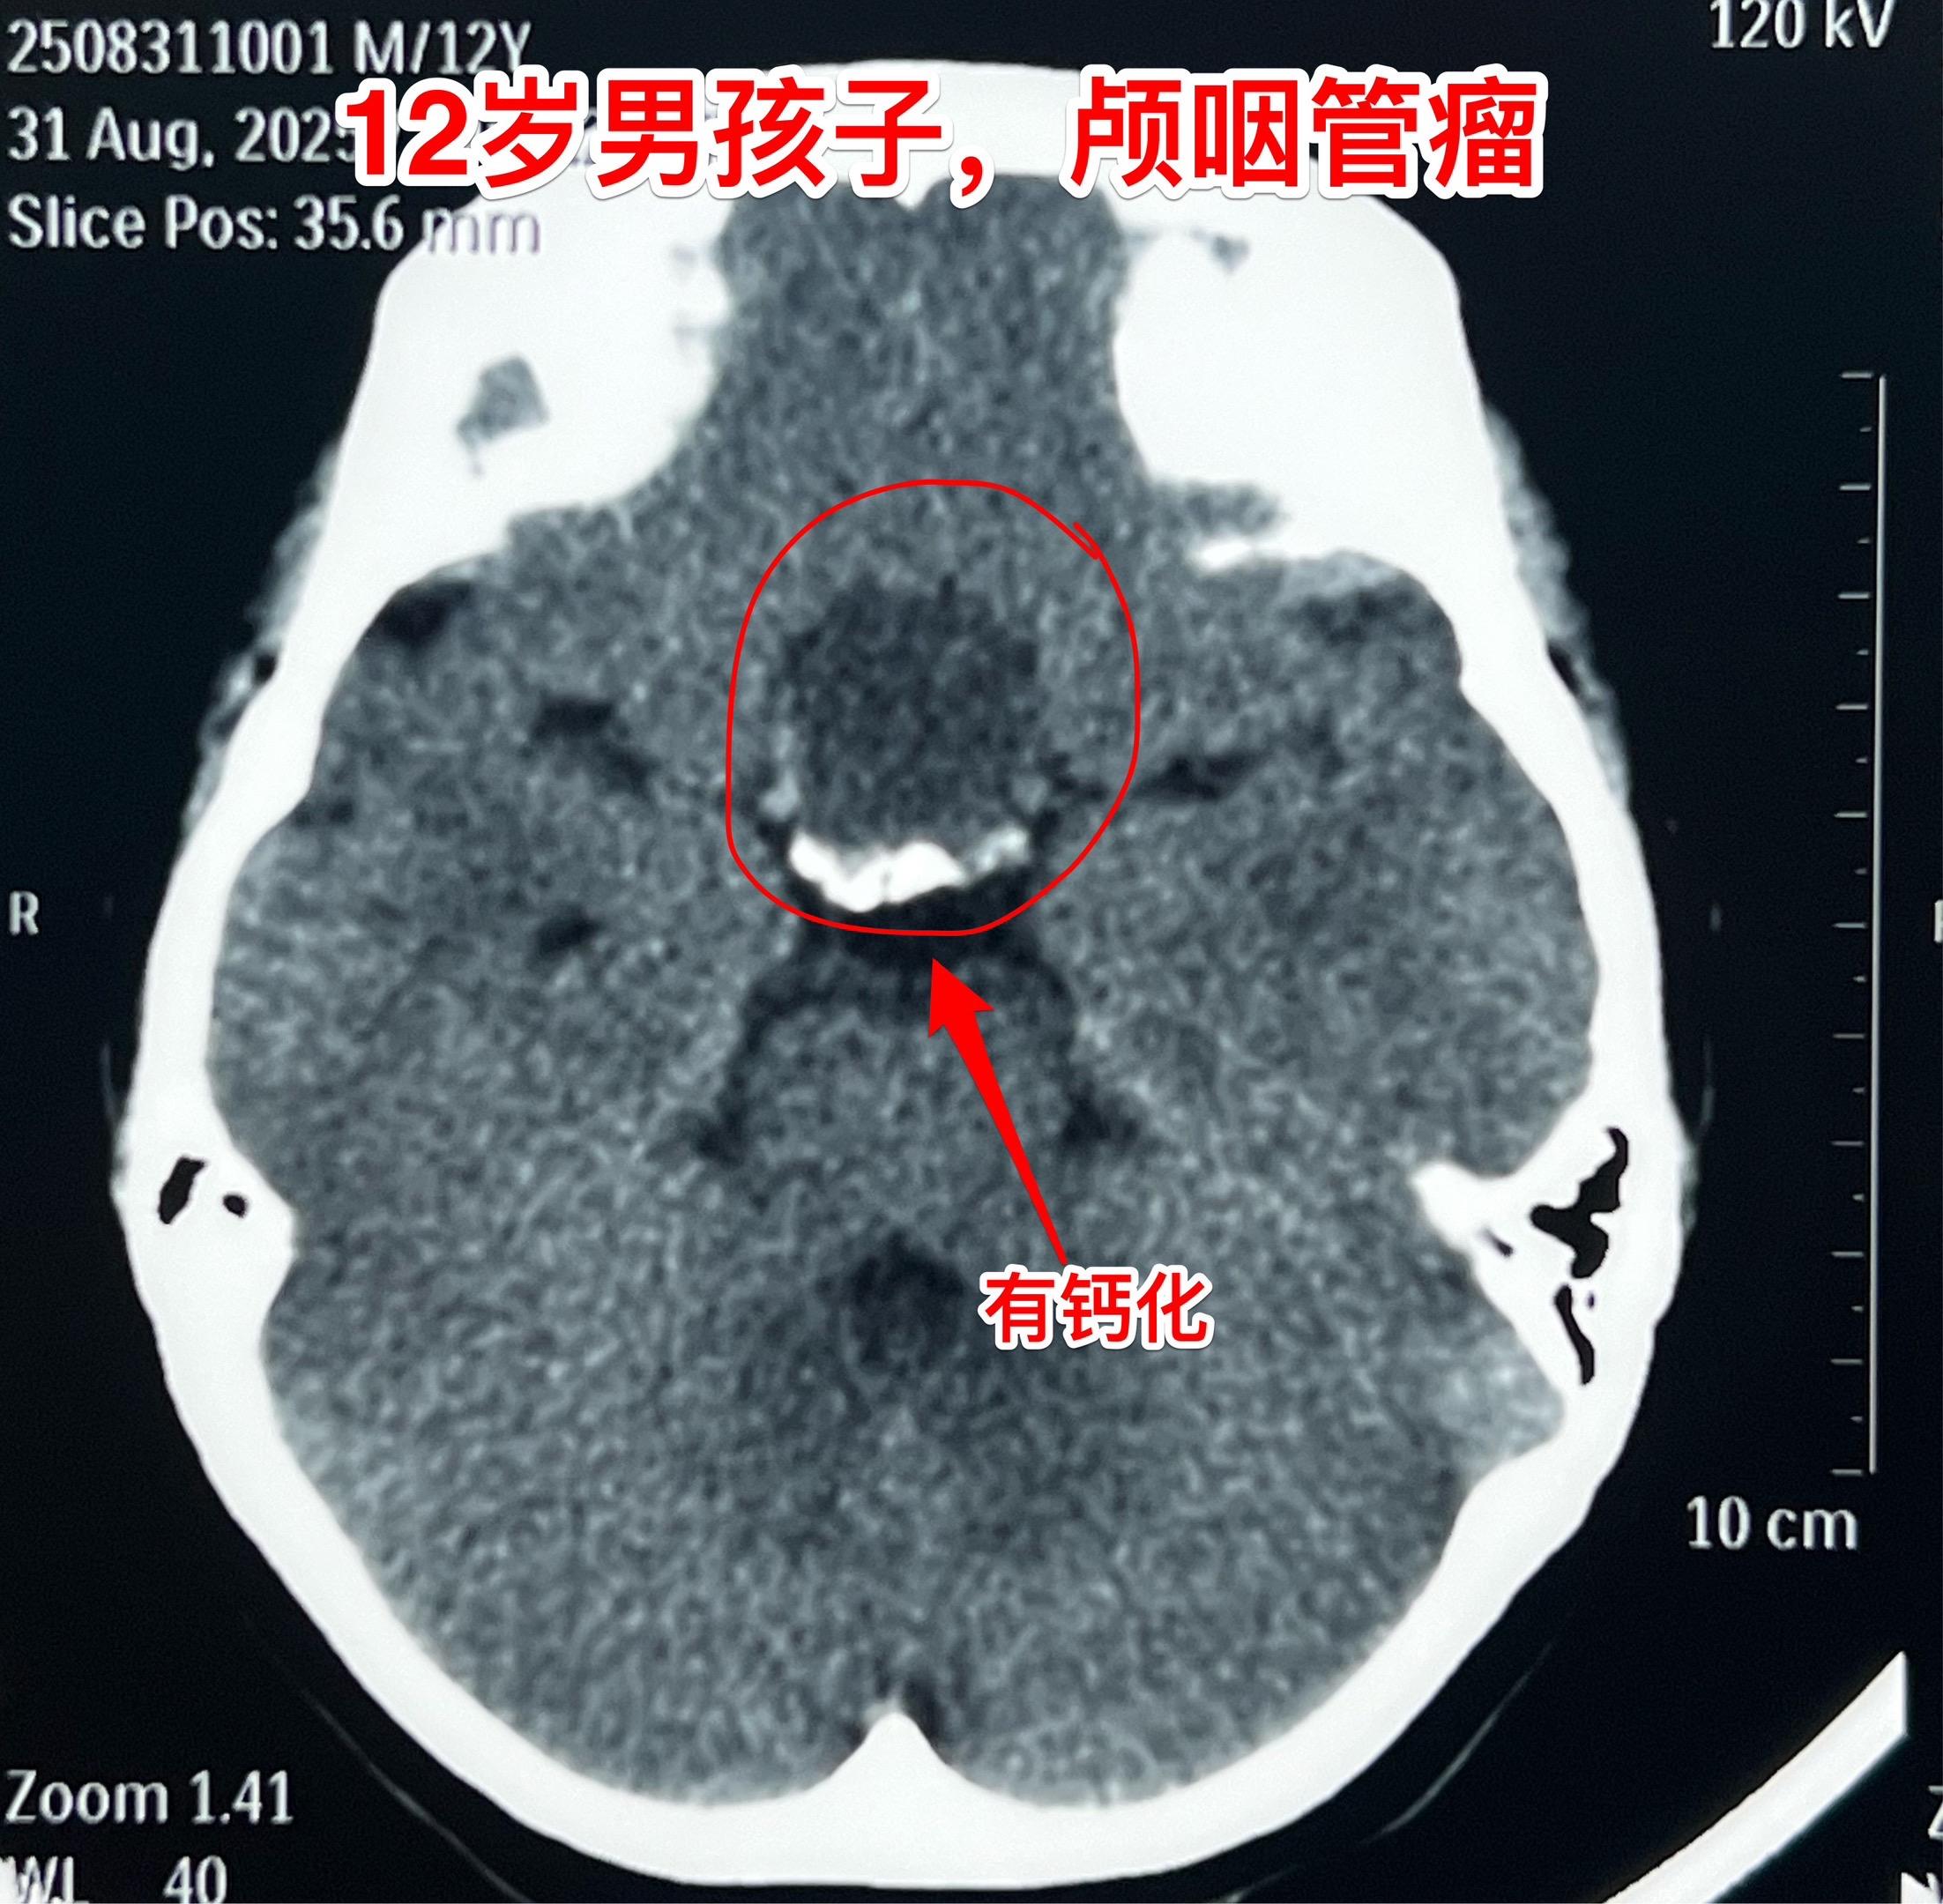

常规一天两个颅咽管瘤手术。今日两个颅咽管瘤手术。 上午第一个是12岁男孩子,江西人。八月份因视力下降到当地医院检查发现颅咽管瘤。八月底找我看病时双眼已经没有有效视力了。 磁共振和CT见图。图2标注:垂体和垂体柄结构清晰,提示在切除肿瘤时垂体和垂体柄很有希望得到保留。 肿瘤切除后垂体柄和垂体保护完好。可以预见男孩子的垂体功能应该会很好👍